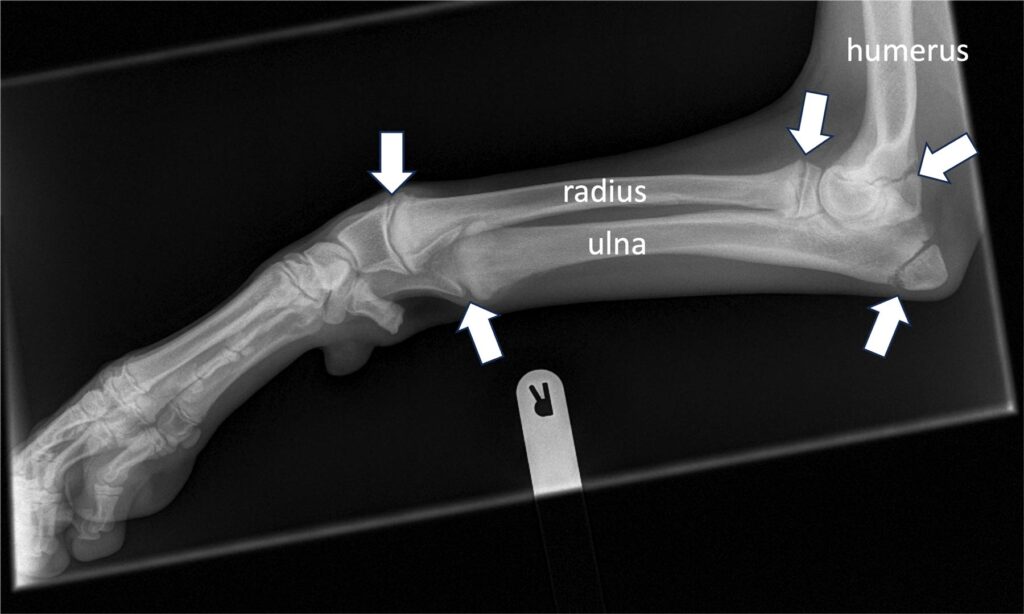

Dogs grow remarkably quickly. If one thinks that a large or giant breed dog is fully grown by 12-18 months of age, compared to a human being, that is a remarkable growth velocity. When vertebrate animals develop, their bones first form as cartilage models, which turn to bone through a process called ossification. Bones gain some of their length from growth at the very ends, but most of it develops at the “growth plate” (also called physes). Cartilage forms to widen the growth plate, and then turns to bone in a “wave” of ossification behind the growing part. Growth plates must grow at the same rate across the growth plate, otherwise the bone might start to deform. In addition, in the antebrachium (the forearm), there are two long bones, the radius and ulna, and so these two bones must grow at the same rate, otherwise there can be bowing of the antebrachium. Not surprisingly, the antebrachium is therefore the most common site of growth deformities in puppies.

Premature closure of antebrachial growth plates

The most common site for growth deformities is the antebrachium. This is because the radius and ulna must grow at the same rate. 85% of the growth of the ulna comes from the distal growth plate and so it is not surprising that the most common growth problem is premature closure of the distal ulnar growth plate. This causes the ulna to act as a ‘bow string’ on the radius and the radius can start to bow (“radius curvus”). Treatment of this problem can take various forms often depending on the age of the puppy. Careful evaluation, planning and monitoring is necessary for best outcomes. If the problem is caught early, sometimes it is possible to influence growth to reduce the deformity. In other cases, it may be necessary to perform corrective surgery to acutely correct the deformity, and in other cases a gradual correction may be performed using external frames and pins.

The pictures here are of a Flat-Coat Retriever who had growth deformities in both legs.